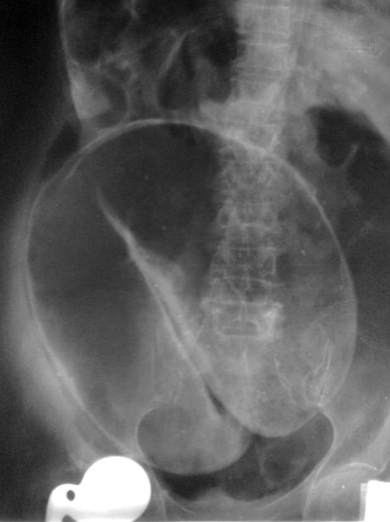

Question 29: What radiological sign is this associated with?

A) Colitis

B) Pneumoperitoneum

C) Caecal volvulus

D) Sigmoid volvulus

E) Small bowel obstruction